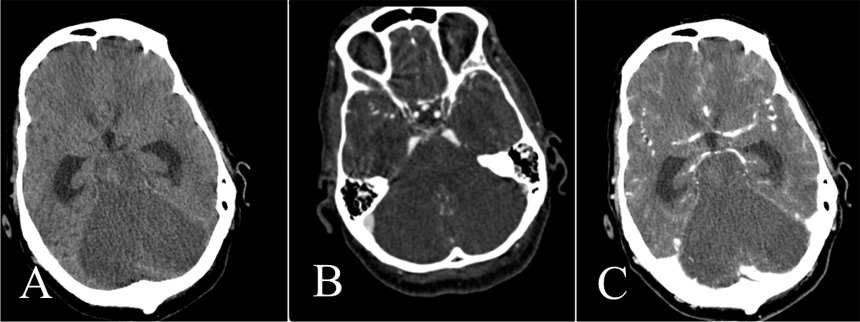

Figure 4

Unenhanced CT (A), CTA (B), and venous-phase CT (C).

Note normal opacification of the supratentorial vessels. Brain death could not be confirmed although there is extensive infarction of the cerebellum, pons and brainstem. The supratentorial ventricles are dilated.

One patient (table 2, no. 25) had extensive ischaemia of the cerebellum, pons and brainstem, the supratentorial territory, however, was nearly normally opacified in the arterial and venous phase (fig. 4) meaning that the criteria of circulatory arrest of the whole brain were not fulfilled. This is an example where the supratentorial brain may still be viable in context of law but the infarction of the brainstem leads to a clinically unreactive coma.